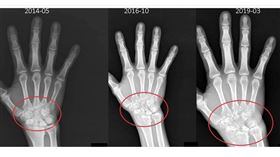

以為不會痛就沒事!類風濕關節炎變骨侵蝕

35歲張姓廚師十多年前診斷出患有類風濕性關節炎,經藥...

2025/07/02 09:51